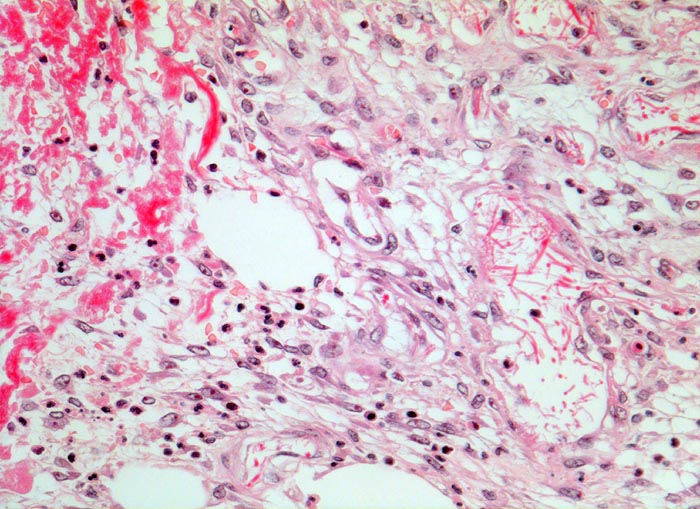

• Zweite Phase: Aufbau von Granulationsgewebe (= zell- und gefäßreiches Bindegewebe). Die Kapillarisierung (Neovaskularisation) durch Einsprossen von Blutgefäßen (Gefäßbäumchen sind als hellrote, glänzende Körnchen im Wundgrund sichtbar) sorgt für ausreichende Ernährung des Gewebes. Die Kollagensynthese durch eingewanderte Fibroblasten benötigt Vitamin C und Sauerstoff.

• Schlitzförmiger, bis in die Subkutis reichender Hautdefekt.

• Neugebildete Epidermis bedeckt im oberen intradermalen Anteil des Wundspaltes teilweise den Gewebsdefekt.

• Daran angrenzender Wundspalt im Bereich des subkutanen Fettgewebes mit Fibrinauflagerungen und ödematösem zellarmem Granulationsgewebe.

• An der Basis des Präparates Auseinanderklaffen des Wundspalts wegen grösserem Blutkoagel (verursacht Wundheilungsstörung).